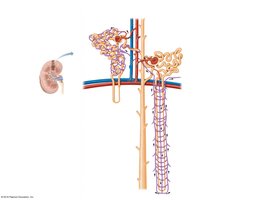

The Nephron

Types and Structure

Nephrons are the microscopic functional units of the kidney. There are two main types:

Cortical Nephrons: 85% of nephrons; located mostly in the cortex.

Juxtamedullary Nephrons: 15%; loops of Henle extend deep into the medulla, crucial for concentrating urine.

Nephron Components

Renal Corpuscle: Includes the glomerulus (fenestrated capillary bed) and Bowman’s capsule (with podocytes forming filtration slits).

Renal Tubules: Proximal convoluted tubule (PCT), loop of Henle, distal convoluted tubule (DCT), and collecting duct.

Renal Tubule Functions

PCT: Major site of reabsorption (glucose, amino acids, vitamins, ions, water) and secretion (ions, toxins, drugs).

Loop of Henle: Reabsorption of water and ions; secretion of urea.

DCT: Reabsorption and secretion of ions; regulated by hormones (aldosterone, PTH).

Collecting Duct: Reabsorption of water (regulated by ADH), urea, and ions; secretion of ions.